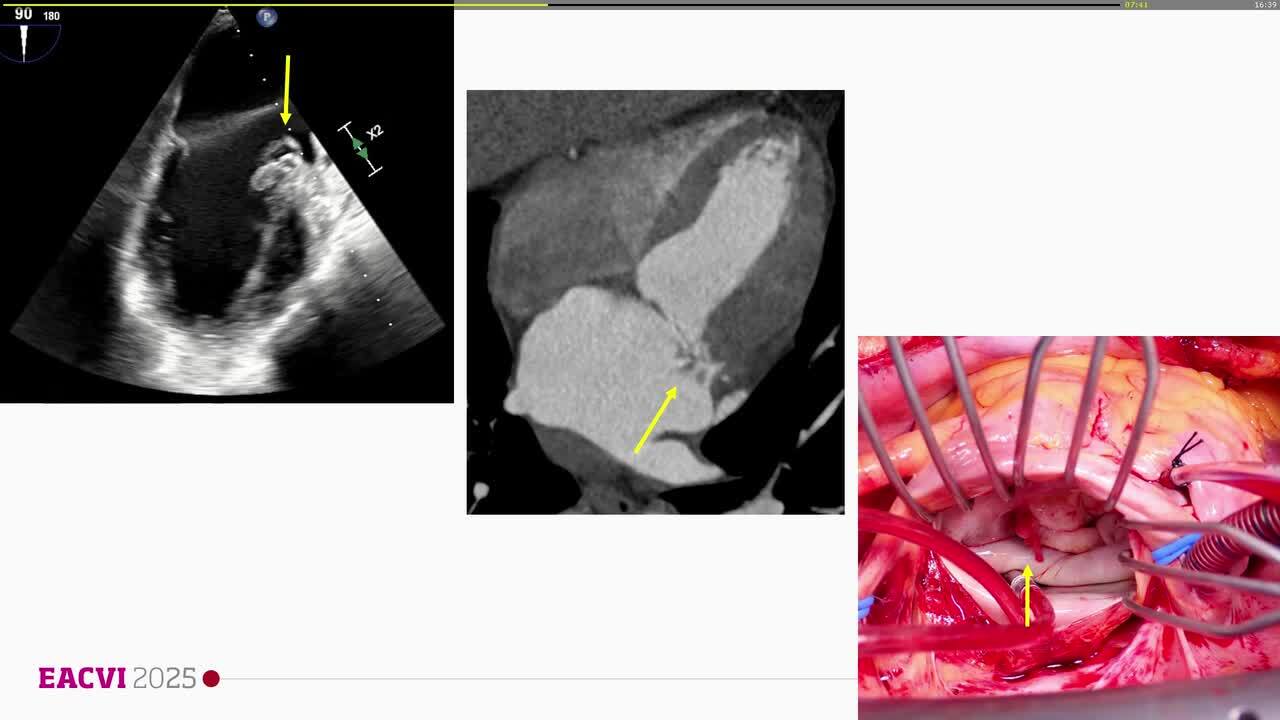

Suspected prosthetic valve endocarditis: a multidisciplinary multimodality approach?